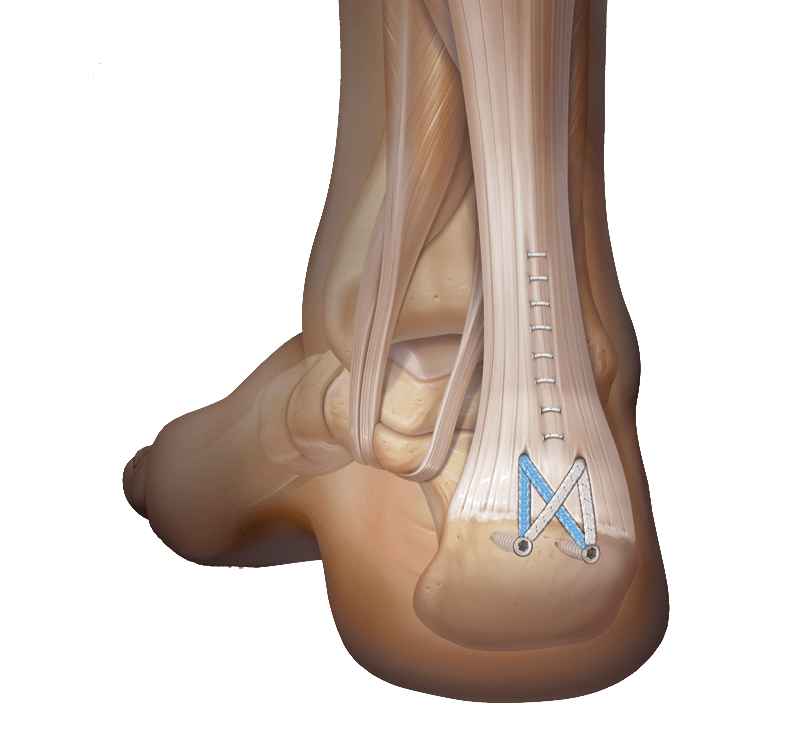

Тендинит Ахиллова сухожилия: симптомы и лечение

Раздел: Картинки на заметку